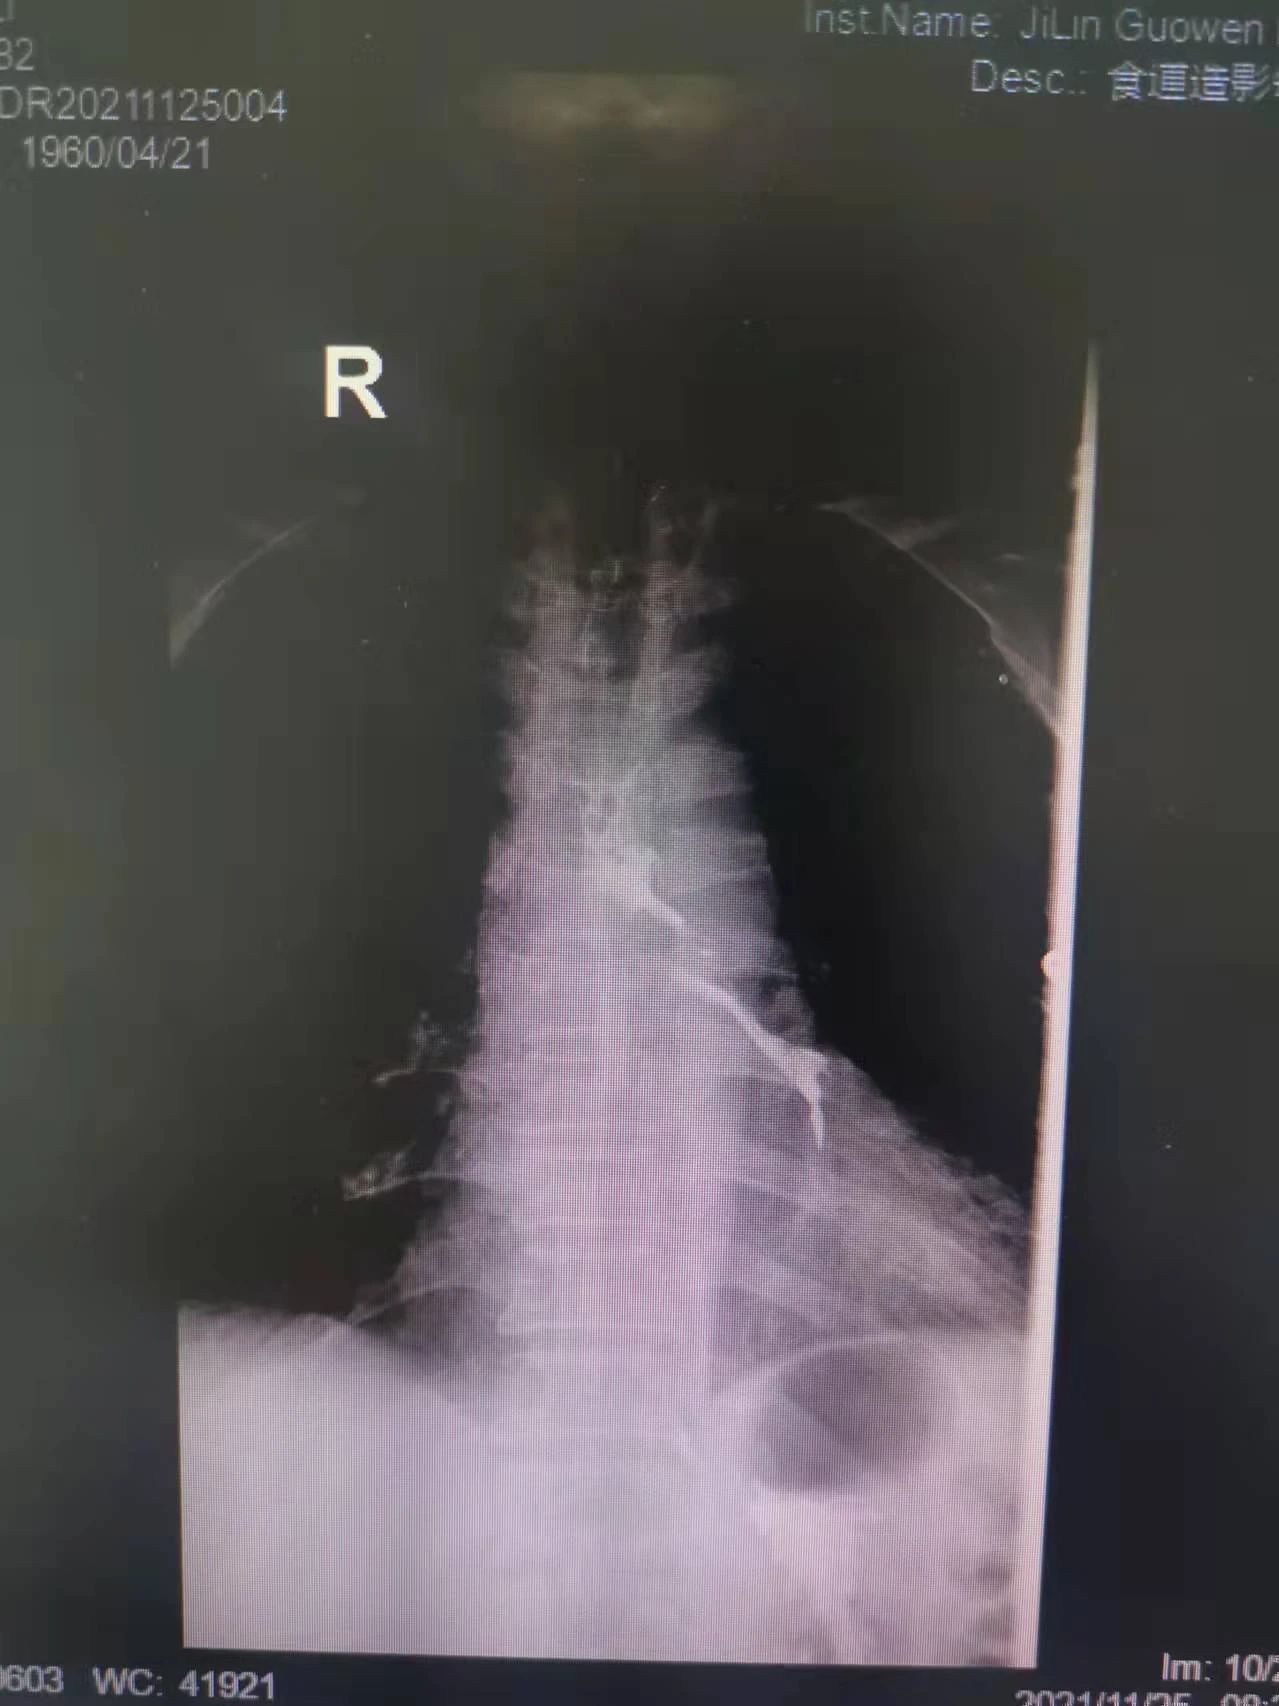

“大夫,我能喝點水么,我嗓子熱”今年61歲的付大爺患有食管惡性腫瘤。起初付大爺進食時吞咽困難,每日進食量極少,后隨著疾病的發(fā)展,付大爺進食后伴隨劇烈嗆咳,經(jīng)系統(tǒng)檢查后,明確診斷為食管氣管瘺。為防止食物進入氣管加重感染,付大爺聽從了醫(yī)生禁食水的意見?,F(xiàn)如今,付大爺每日不光承受著癌癥所帶來的疼痛,還要承受著禁食水后仿佛置身于沙漠般的口干舌燥。這段時間里,喝一口水這么一個小小的愿望對于他來說都已成奢求!有著正常食欲卻無法進食,可以想象對于人的生理及心理帶來多么大的創(chuàng)傷。家屬眼見付大爺痛苦不已,也是焦急萬分。

在這種情況下,我院介入二科侯主任決定通過介入治療中的食管支架植入來幫助患者實現(xiàn)這個愿望。手術當日,侯主任在機器的幫助下,將一根細細的導絲穿過腫瘤到達付大爺胃部,然后再沿著導絲,把壓縮好的支架放在腫瘤里面。通過后撤導管,把壓縮的支架打開,支架把腫瘤撐開,讓食管不再堵塞。有了支架的支撐,付大爺就可以自由地吃東西了,哪怕食管和氣管有溝通,因為支架覆蓋了腫瘤,通道堵住了,吃的東西也不會吸到肺內造成感染。這時痛痛快快地吃上一頓,也不再是奢望!

手術很順利,付大爺也在術后第2天喝到了自己日思夜想的清水,露出了久違的笑容。從某種意義上講,介入食管支架置入術的成功實施,付大爺不能進食的病已經(jīng)“治好”了,雖然從生理角度來說,付大爺可以通過終生使用腸內營養(yǎng)來維持生存,但我們所做的是致力于給予患者更好的生存體驗,或者說是尊嚴。銘記并保持一名醫(yī)者的初心,我們要做的正如那句著名的墓志銘所說:有時去治愈,常常去幫助,總是去安慰。